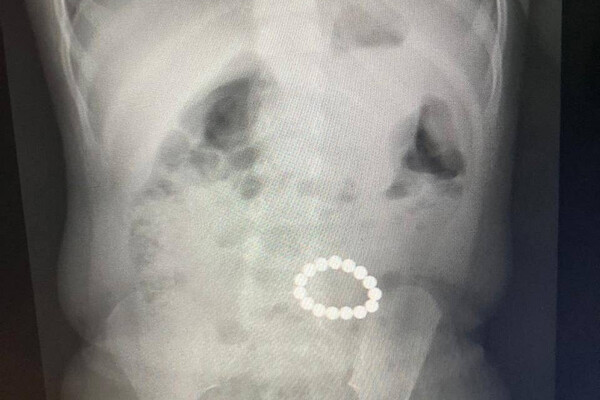

Девятимесячную пациентку доставили в медучреждение на скорой. Мать ребенка рассказала, что дочь съела несколько деталей от конструктора. Диагностика показала, что девочка проглотила гораздо больше деталей, чем предполагала ее родительница: рентген показал скопление в кишечнике 15 инородных предметов.